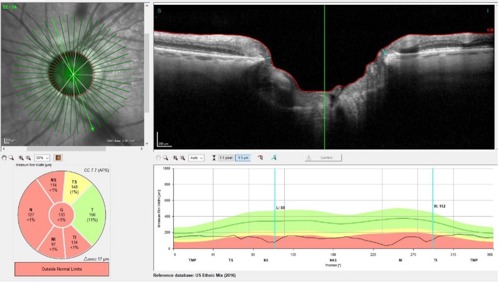

This leaves us just one remaining metric upon which to base clinical judgements for managing this patient’s glaucoma: the BMO-MRW readings, as shown in Figure 3.

The BMO-MRW readings are taken as a series of radial scans from the center of the optic nerve outward, compensated for the foveal center, which usually sits slightly below horizontal. This scan area is completely unaffected by the ERM and therefore gives us reliable data with which to judge the stability of the glaucoma.